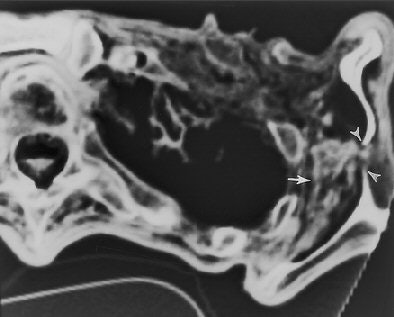

![]() |

| Transverse CT section (obtained on May 3, 1994) through the left shoulder region (caudal to the prehistoric arrowhead) shows an inhomogeneous area of attenuation (dehydrated hematoma, arrow) between the lateral rib cage and the scapula. Note the discontinuity in the ossified body of the scapula and the wispy soft-tissue opacity (hematoma) that extends through the bone defect (arrowheads). Authors speculate that the arrowhead and a portion of the arrow shaft penetrated the scapula in this location and that blood from the deep hematoma followed the arrow track into the subcutaneous tissues. Fig. 23, Murphy WA, zur Nedden D, Gostner P, et al. "The Iceman: Discovery and Imaging," Radiology 2003; 226:614-629. |

The CT images also displayed hyperattenuating areas that were interpreted as dehydrated remnants of a hematoma, as well as evidence of a perforation of the scapula, the researchers stated. After inspecting the mummy's back when the arrowhead was discovered, the researchers found a small skin laceration over the scapula. They hypothesized that the arrow entered the left shoulder from the rear, passed through the scapula, and injured a major vessel, resulting in a hematoma.

"Furthermore, it is speculated that when the arrow was withdrawn, the overlying scapula interfered and caused the arrowhead to separate from the shaft. Thus, the arrowhead remained trapped between the rib cage and the scapula," Murphy and colleagues wrote. "The fact that the arrow entered the iceman from behind suggests that the manner of death was either accidental or homicide."